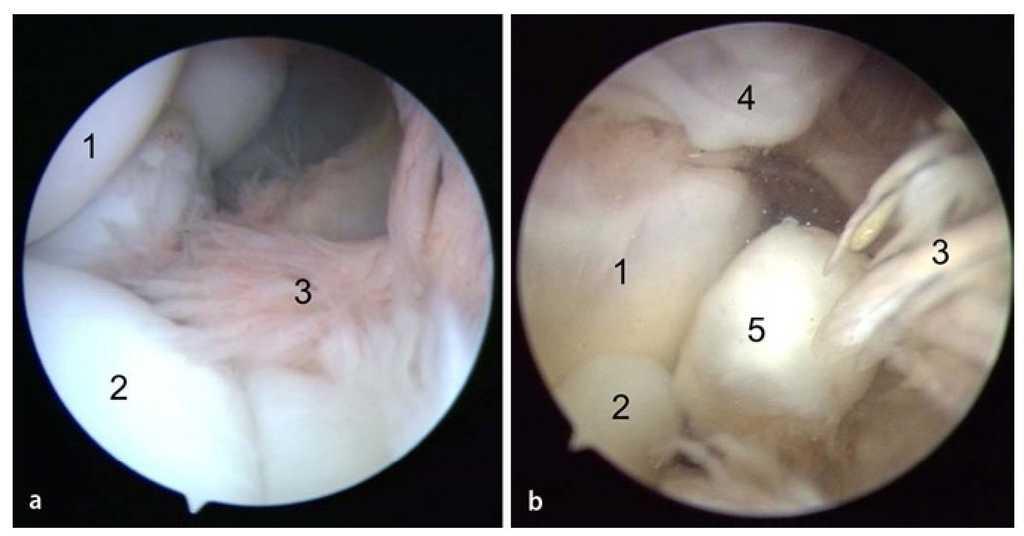

Fig. 8 a) Mediante un artroscopio estándar (ángulo visual de 30º) es posible visualizar el compartimento anterior. Primero se observa el húmero distal (1), la cabeza del radio (2) y el tejido sinovial (3). b) A continuación se desplaza el artroscopio más hacia el interior del compartimento anterior. Aquí se pueden observar la tróclea humeral (1), el proceso coronoides (2) y el tejido sinovial (3). Con frecuencia se observan osteofitos (4) en la zona del húmero anterior, así como cuerpos articulares libres (5).

Fig. 14 La artroscopia en el compartimento posterior se inicia con la realización del abordaje dorsorradial y del abordaje transtendinoso desde el cual se introducirán los instrumentos (Figs. 6c). En el ángulo visual de la cámara por encima del portal posteroradial se encuentran la punta del olécranon y la fosa olecraniana. a) Con frecuencia existen adherencias masivas en la zona de la fosa olecraniana, que se separan con un resector sinovial y se extraen. b) En los casos con graves limitaciones de movimiento se puede realizar también una cirugía de la fosa con una fresa para hueso (no se representa en la imagen). Mediante esta cirugía se extraen las formaciones óseas molestas, así como formaciones osteofíticas en la zona de la fosa olecraniana, hasta que se restituye la libre movilidad entre el olécranon y la fosa olecraniana.

Fig. 15 a) Las formaciones osteofíticas en la zona del olécranon se extraen mediante un pequeño cincel Lambotte (5-6 mm) a través del portal transtendinoso. b) Después de haber desprendido los osteofitos, estos se extraen con una pinza de agarre. Para que la unión sea suave, se puede alisar la zona con un resector sinovial. Para finalizar, se verificará y documentará el rango de movimiento, se introducirá un drenaje de Redon en la articulación y se cerrarán los abordajes mediante una sutura de punto simple.

Fig. 16 Para la documentación de los resultados de la intervención quirúrgica se realiza un control radiológico en dos planos del codo antes del alta del paciente. a, b) Se pudieron extraer los osteofitos humerales presentes en el preoperatorio (flechas).